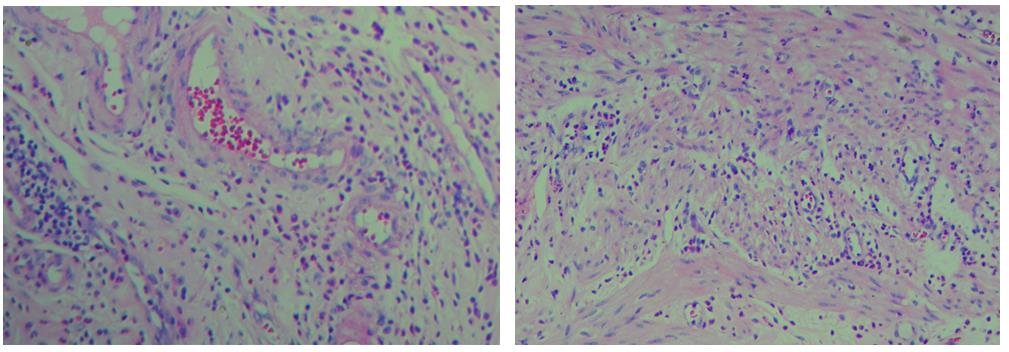

3、色彩鮮艷,核漿紅藍對比鮮明,染色效果持久穩(wěn)定,胞核結構清晰

細胞中的細胞核由帶負電荷的酸性物質組成,與帶正電荷的堿性染料蘇木素的氧化物三氧化蘇木紅有較強的親和力;而細胞漿則相反,因含有帶正電荷的堿性物質而與帶負電的酸性染料曙紅Y的親和力較強;細胞或組織切片經(jīng)HE染色后,細胞核被染成藍紫色,細胞漿、紅細胞、肌纖維、膠原纖維、結締組織、嗜伊紅顆粒等被染成不同程度的紅色、粉紅色或橙紅色,與藍色的細胞核形成鮮明的對比,因此更易于觀察細胞或組織中正常成份和病變成份的一般形態(tài)結構。

【實際染色效果】